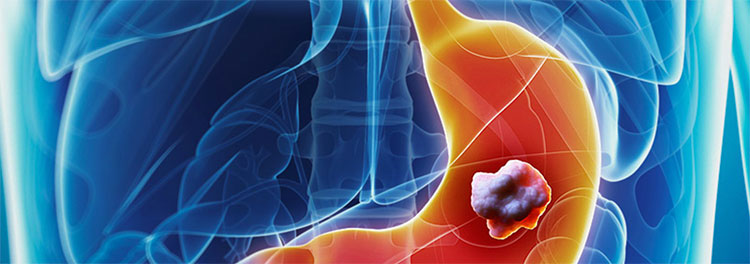

SIGNOS Y SINTOMAS DEL CÁNCER GÁSTRICO

La gran mayoría de nuestra población se diagnostica en etapas avanzadas, esto se debe a la casi nula presencia de signos y sintomas de tumores en etapas tempranas; por otro lado al hecho que la mayoría tienen el concepto erróneo que "SI NO DUELE NO ES GRAVE" y por tanto no amerita una evaluación.

En conclusión, debido a la sintomatología inespecífica se suele asociar a otras enfermedades como gastritis, reflujo gastroesofagico o úlcera gástrica. Por tanto, ante cualquier sintomatología gastrica es necesario RECURRIR A UNA ENDOSCOPIA.